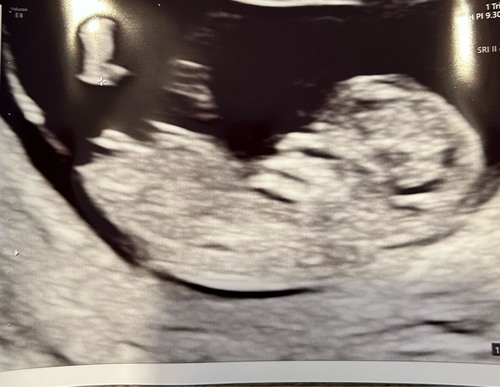

Een broertje of zusje voor ons zoontje?

Broertje!💙